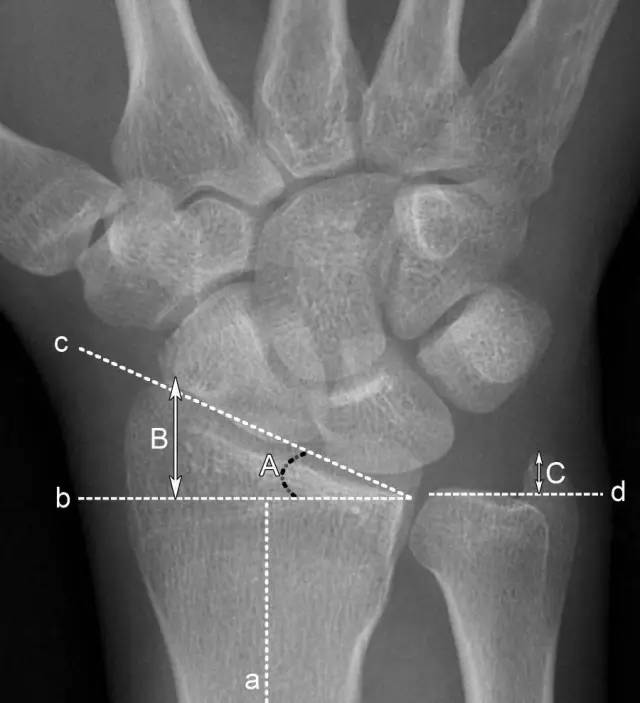

2、腕关节常用测量数据

A.桡骨内倾角:正常为15°-35°。若此角度改变,提示桡骨远端骨折或腕关节脱位;

B.桡骨茎突长度 :正常为8-18mm,且桡骨茎突较尺骨茎突低1-1.5cm。若此长度改变,提示桡骨远端骨折;

C.尺骨茎突长度:正常为2-8mm。若此长度改变,提示尺骨茎突骨折或尺骨茎突过长,易引发尺骨茎突撞击综合征。

a.桡骨纵轴线 b.桡骨纵轴线垂线 c.桡骨远端关节面切线 d.尺骨远端关节面水平线 A.桡骨内倾角 B.桡骨茎突长度 C.尺骨茎突长度